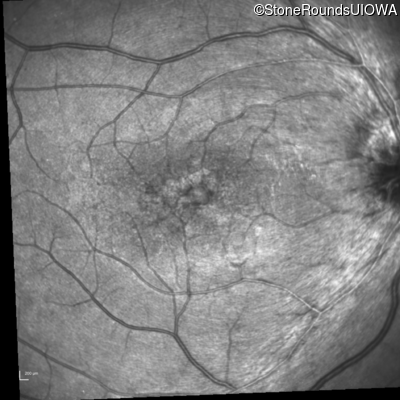

Infrared Fundus Photograph - Right - 20/30 -2

Exemplar